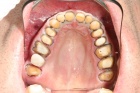

Leicht und praxisorientierte Fortbildung, um fit für das erste eigene Implantat zu werden. Halten Sie den Anschluss und bleiben konkurrenzfähig mit Ihren Kollegen.

Erfahren Sie, welche Fehler Sie unbewusst beim Implantieren machen können. Lernen Sie Ihr eigenes Implantat System anhand des Bohrprotokolls einschätzen und zu beurteilen. Wichtige knochenbiologische Kenntnisse.

Eignen Sie sich wissenschaftlich aktuelles Wissen an und vermeiden Misserfolge, die sich bisher nicht erklären konnten. Warum verkürzt eine perfekte Primärstabilität die Einheilzeit.